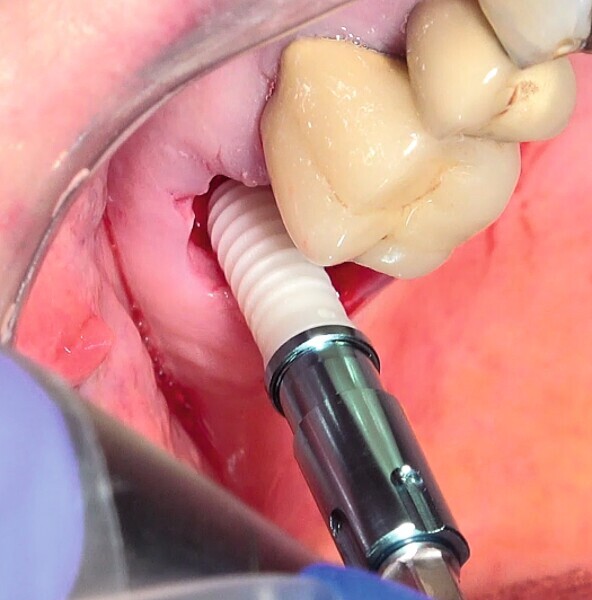

Fig. 27 : Pose de l’un des implants deux pièces en céramique au niveau tissulaire.

Fig. 28 : Pose de l’un des implants deux pièces en céramique au niveau tissulaire.

La crête alvéolaire au niveau du site de la molaire inférieure était trop étroite pour permettre la pose prédictible d’un implant sans une augmentation osseuse préalable. Des implants deux pièces en zircone ont été mis en place, simultanément à une augmentation osseuse latérale, au moyen d’une allogreffe et d’une membrane de collagène résorbable (Figs. 25–34).